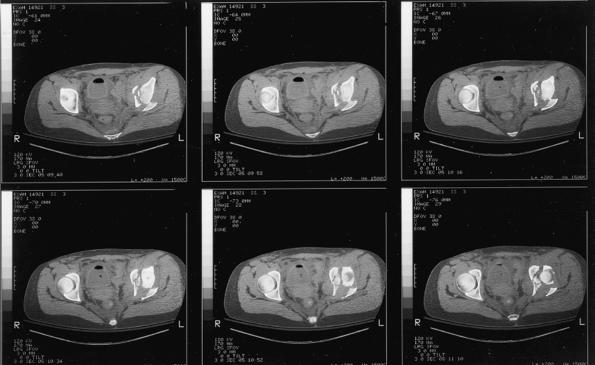

![]() |

Figure 41.4.

Initial AP pelvis x-ray of a 19-year-old woman involved in a motor vehicle accident. The left hip is dislocated, and there is a transverse fracture of the left acetabulum. A double density just superior to the dislocated femoral head suggests a posterior-wall fracture component. |